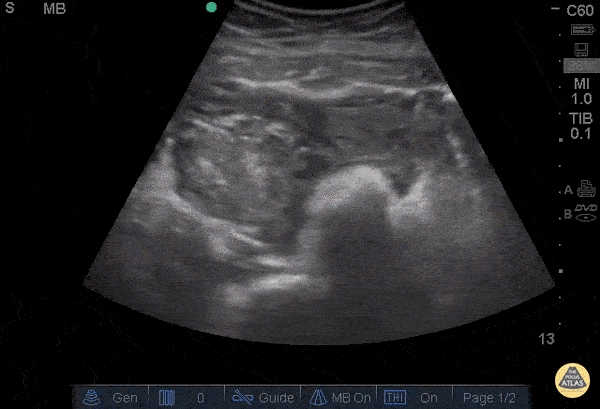

OB/Gyn - Ruptured Ovarian Cyst - Hematoma

28 year-old female was BIBEMS after a witnessed syncopal episode at home. The patient endorsed abdominal pain that started during intercourse that morning and had been getting worse. On arrival, the patient appeared pale and diaphoretic. The patient’s FAST exam was performed immediately and showed free fluid in the RUQ and LUQ. The suprapubic view showed a large pelvic hematoma. The patient was evaluated by the GYN service and was taken emergently to the OR where she was found to have a ruptured cyst. Don't forget, the FAST can be used for more than trauma. Dr. Guru Shan and Dr. Catherine Bon - Kings County Emergency Medicine